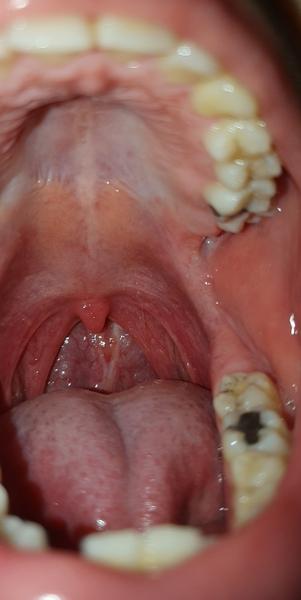

mám 19 rokov a chcel by som sa poradiť ohľadom môjho problému. Už viac ako mesiac ma trápi škriabanie v hrdle. Krvné testy aj výter na baktérie boli v poriadku. Okrem toho som si všimol aj malý výrastok na podnebí (vľavo na foto) spolu s akýmsi vrásením medzi tvrdým a mäkkým podnebím, ktoré som si doteraz nevšimol. Tento výrastok však mám už asi 4 mesiace.

Mám sa obávať nádoru, alebo ide iba o nejakú cystu?

Na prstoch mám už dlhšie bradavice, tak by ma zaujímalo, či môže prípadne ísť o ústne HPV. Keď vytvorím tlak na podnebie, cítim miernu bolesť.

na základe priloženej fotografie nebadám prítomnosť cysty ani slizničných prejavov HPV, ale stanovenie diagnózy si vyžaduje komplexné vyšetrenie v zubolekárskom kresle, preto v prípade pozorovania akýchkoľvek zmien na sliznici ústnej dutiny, ktoré pretrvávajú dlhšiu dobu, odporúčam navštíviť zubného lekára, prípadne sa nechať odoslať za špecialistom - parodontológom, stomatochirurgom alebo ušno-nosno-krčným lekárom.

Ústne prejavy (napr. podtypy HPV 6, 11) sú zväčša belavé drsnejšie vystúpenia, niekedy s typickým karfiolovým tvarom na úzkej báze, často sa vyskytujú z vnútornej strany pier, na sliznici líc, na jazyku - je potrebné vyšetriť celú ústnu dutinu.